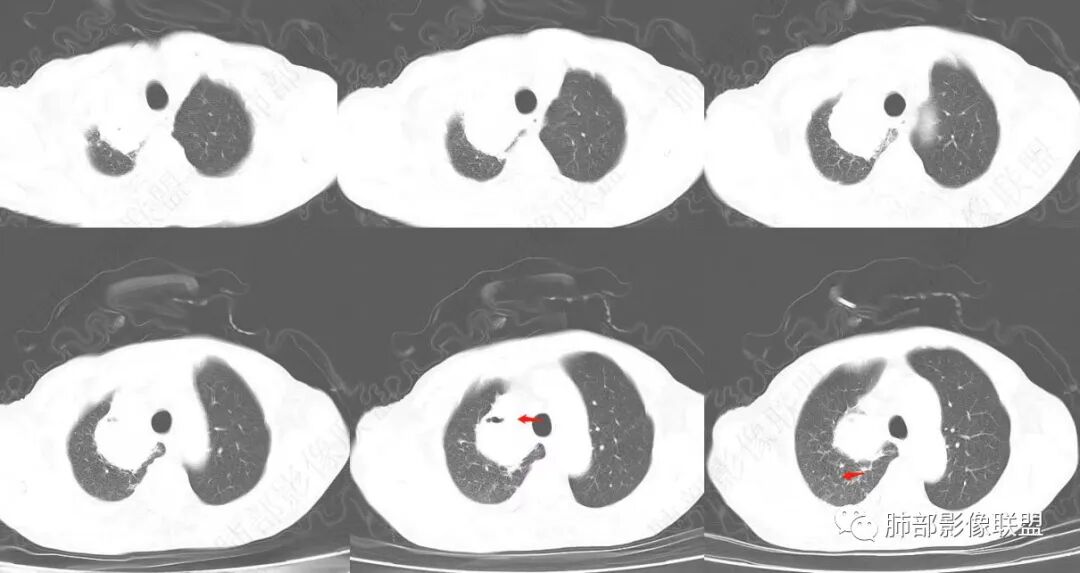

我就在想这个感染如何继发的?

近端的支气管如何改变?

感染了:腔内就出现液气平面,附近大片高密度影

治疗后,腔内含气病灶少了

说明支气管通畅——狭窄——堵塞

我怀疑是不是堵塞口通了,腔内的坏死物播散到附近肺组织

抗炎后转后,支气管又收缩,堵了

也就是一元,二元的问题

是原有病变继发感染

还是单一感染的问题

患者有高血压、脑梗死、肾结石病史,因左胸痛不适入院,伴高热,血常规示白细胞、中性粒细胞高。胸部CT示右肺上叶肿块影,边缘模糊影,内可见低密度坏死,边界清楚,一月后出现气液平面,周围渗出,治疗2周复查液平及周围炎症吸收,肿块未见明显吸收。

考虑肿瘤?右肺上叶高密度影,边缘模糊,侵及纵隔及胸廓入口,病灶密度不均匀,部分支气管截断,增强后不均匀强化,内可见较大范围坏死,纵隔多发肿大淋巴结不均匀强化。肺上沟瘤不能排除。

感染性病变?右肺上叶尖段团块影,中央见大片状状坏死伴液气平面,周围见斑片状高密度影,实验室检查血象明显升高,抗炎治疗后,病灶有所吸收缩小,灶周斑片状消失。